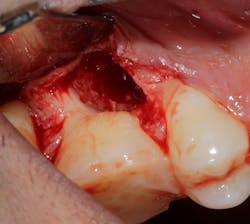

Saving compromised multirooted teeth with root amputation can often be successful, but the technique is sensitive and complex. Proper case selection is essential, and considerations include the following:

There is sufficient bone support around the remaining roots (at least 50% or more is needed) along with sufficient coronal tooth structure (figure 3).How does root amputation compare with other surgical procedures?